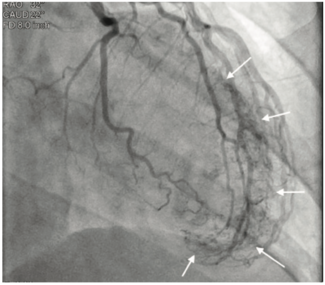

A 60-year-old female with no significant past medical history presented with recurring chest discomfort, elevated troponin, and systolic murmur.